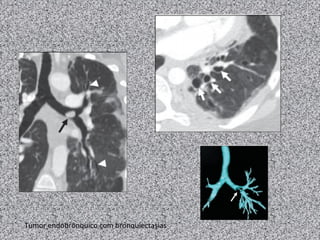

Bronquiectasia focal

Tumor endobrônquico com bronquiectasias

Broncolitíase

Estenose congênita BPE